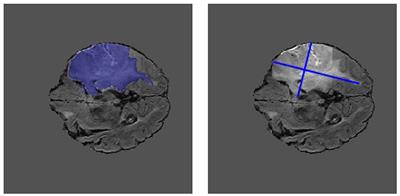

State-of-the-art multi-modal brain tumour segmentation methods often rely on large quantities of manually annotated data to produce acceptable results. In settings where such labelled data may be scarce, there may be value in exploiting cheaper or more readily available data through clinical trials, such as Response Assessment in Neuro-Oncology (RANO). This work demonstrates the utility of such measurements for multi-modal brain tumour segmentation, whereby an encoder network is first trained to regress synthetic "Pseudo-RANO" measurements, using a mean squared error loss with cosine similarity penalty to promote orthogonality of the principal axes.Using oriented bounding-boxes to measure overlap with the ground truth, we show that the encoder model can reliably estimate tumour principal axes with good performance. The trained encoder was combined with a randomly initialised decoder for fine-tuning as a U-Net architecture for whole tumour (WT) segmentation. Our results demonstrate that weakly supervised encoder models converge faster than those trained without pre-training and help minimise the annotation burden when trained to perform segmentation.